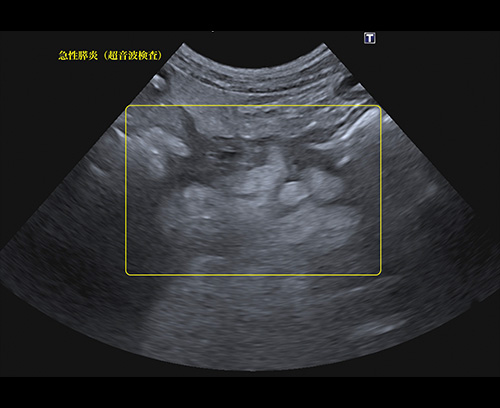

急性膵炎